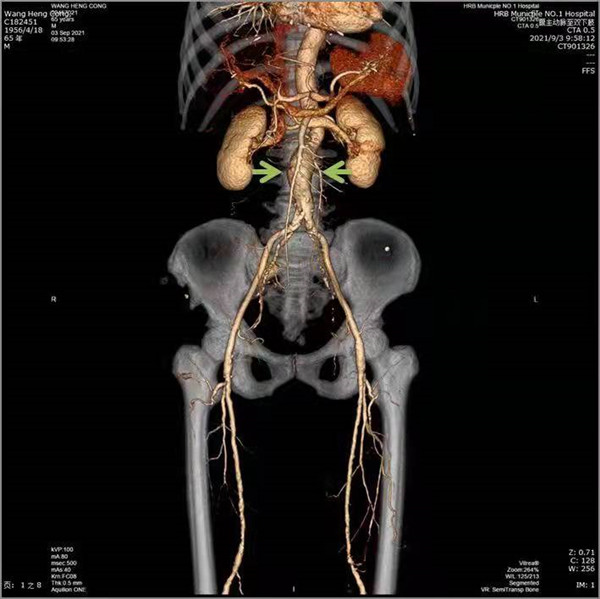

近日,家住哈市的王大爺遇到了煩心事,肚子總是漲漲的,雖然不疼但總是不舒服,一吃點東西會更加嚴重。本以為是消化不良,過幾天自然就緩解了,不成想這一過就是一個多月,症狀不但沒有緩解,反而越來越重,這才引起了重視。更鬧心的是看了好幾家醫院,檢查沒少做卻找不到原因。最終慕名前往哈爾濱市第一醫院就診,經過普外三科周偉忠主任醫療團隊的仔細診查,原來是得了「腹主動脈瘤合併腸繫膜上動脈狹窄」。

術前

腸繫膜上動脈狹窄臨床發病率低、發病隱匿、症狀不典型,常和其他腹部疾病混淆。臨床醫生對這種疾病的認識不足導致慢性腸繫膜缺血患者的診斷延誤、診斷不足和治療不足,可能造成致命的急性腸繫膜缺血而死亡。本例患者是以腸繫膜動脈缺血症狀就診,同時發現了腹主動脈瘤,這種情況很少見。

由於患者高齡、基礎疾病較多,如同時行兩種手術,存在較高風險,但病人強烈希望能夠一起解決這兩個問題,經全面評估考慮,周偉忠主任決定兩種疾病同時處理,行微創腔內治療。術前詳細測定患者病變段血管數據,制定了周詳的手術方案,在周偉忠主任帶領下,瞿鵬、劉焱喆醫生及麻醉醫生、導管室配合下實施手術。藝高人膽大,術中,周偉忠主任團隊於主動脈放置覆膜支架隔絕腹主動脈瘤,腸繫膜上動脈支架植入使腸繫膜上動脈血流恢復。手術順利完成。術後患者恢復良好,術後三天即下地活動,患者腹痛、腹脹症狀消失,一周後出院。